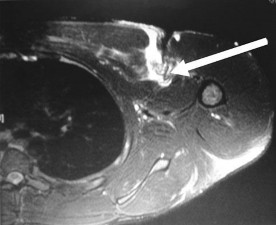

A 31-year-old volleyball player presents with deep posterior shoulder pain. MRI arthrogram reveals a posterior labral tear with an associated large paralabral cyst extending into the spinoglenoid notch. Clinically, this patient is most likely to exhibit which of the following isolated motor deficits?

Explanation

The suprascapular nerve innervates the supraspinatus muscle before passing through the spinoglenoid notch. A cyst located strictly at the spinoglenoid notch will compress the nerve distally, causing denervation exclusively to the infraspinatus. This results in isolated weakness in external rotation, while abduction (supraspinatus) remains intact.